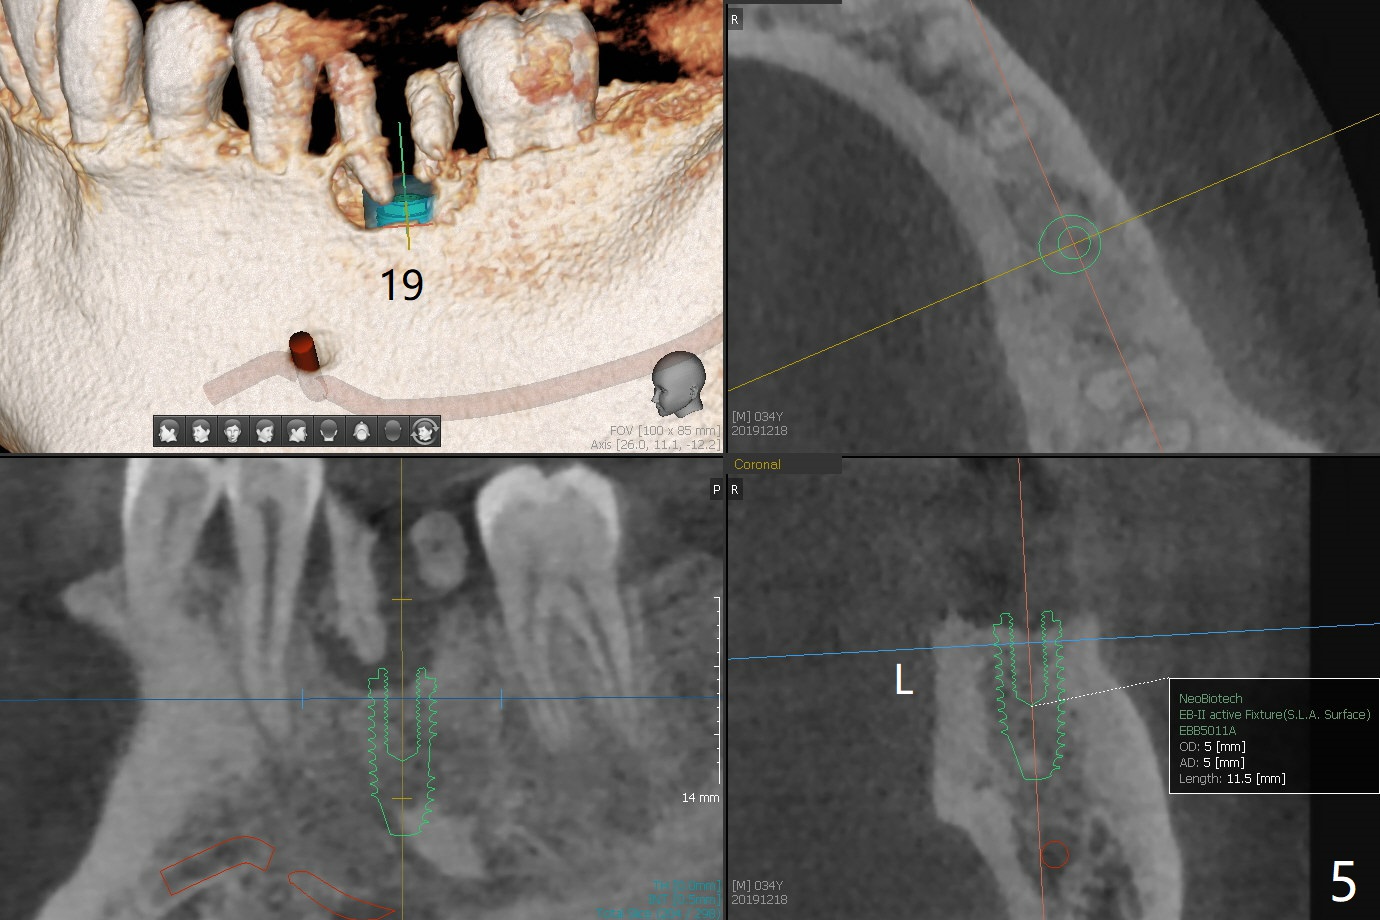

A 34-year-old man (smoker 1/2 ppd) presents to clinic for SRP and implant consultation (Fig.1). He wishes to restore UL first and the rest 2nd (Fig.2-5). Pay attention to placement level. OH will be emphasized, water pik and smoke cessation.